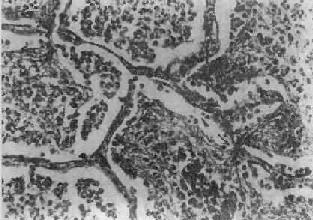

图9-15 大叶性肺炎 肺泡腔内充满纤维素性渗出物,纤维素丝穿过肺泡间孔,使相邻肺泡内的纤维素网互相连接